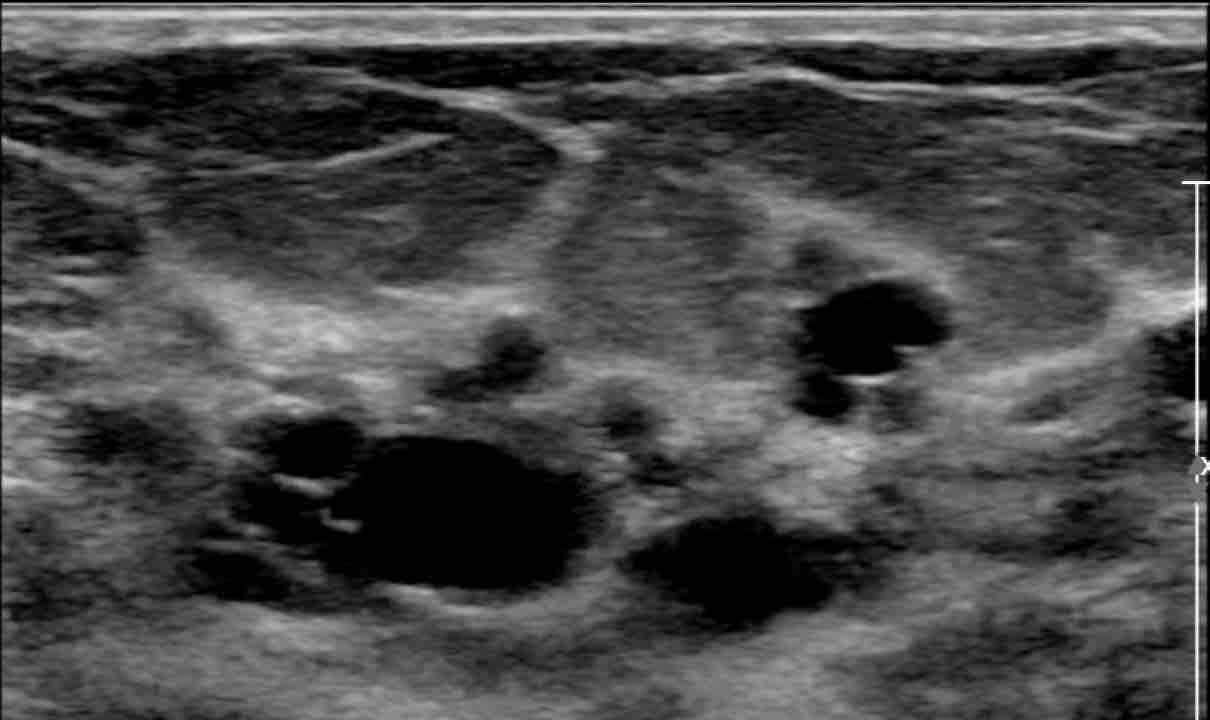

An ultrasound image of breast cyst. Download Scientific Diagram Does Heat Help Breast Cysts This test can help your doctor determine whether a breast lump is fluid filled or solid. Breast cysts can occur at any age but are most common between ages 30 and 49. Understanding the difference between breast cysts and tumors, recognizing the symptoms of breast cysts, and utilizing diagnostic tools like ultrasound can help women make informed decisions about their. Does Heat Help Breast Cysts.

Cluster Of Cysts In Breast Ultrasound Clusterisasi Does Heat Help Breast Cysts How i healed my breast cysts naturally with food, essential oils, herbs, emotional clearing, and intuitive healing. They are usually noncancerous (benign). Understanding the difference between breast cysts and tumors, recognizing the symptoms of breast cysts, and utilizing diagnostic tools like ultrasound can help women make informed decisions about their breast health. This test can help your doctor determine whether. Does Heat Help Breast Cysts.